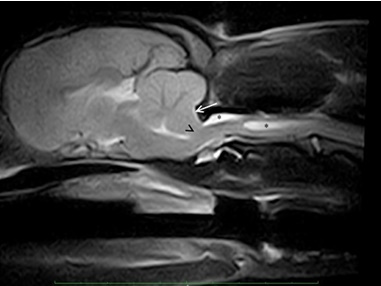

MRI (ακολουθία Τ2) μέσης οβελιαίας τομής του εγκέφαλου και της προσθίας αυχενικής μοίρας του νωτιαίου μυελού σε σκύλο Cavalier King Charles Spaniel, 2 ετών με επίμονες και επαναλαμβανόμενες κινήσεις «ξυσίματος» στην περιοχή του αυχένα με το οπίσθιο άκρο.

Απεικονίζεται αύξηση των διαστάσεων του κεντρικού σωλήνα με ραχιαία επικοινωνία με τον υποσκληρίδιο χώρο κατά μήκος του Α2 λόγω αυξημένης συγκέντρωσης ΕΝΥ (*). Το εύρημα αυτό είναι συμβατό με συριγγο/υδρομυελία. Επίσης, απεικονίζεται δυσπλασία του ινιακού οστού (βέλος) και η συμφόρηση/κήλη του οπισθίου τμήματος του σκώληκα της παρεγκεφαλίδας διαμέσου του ινιακού τρήματος (κορυφή βέλους).